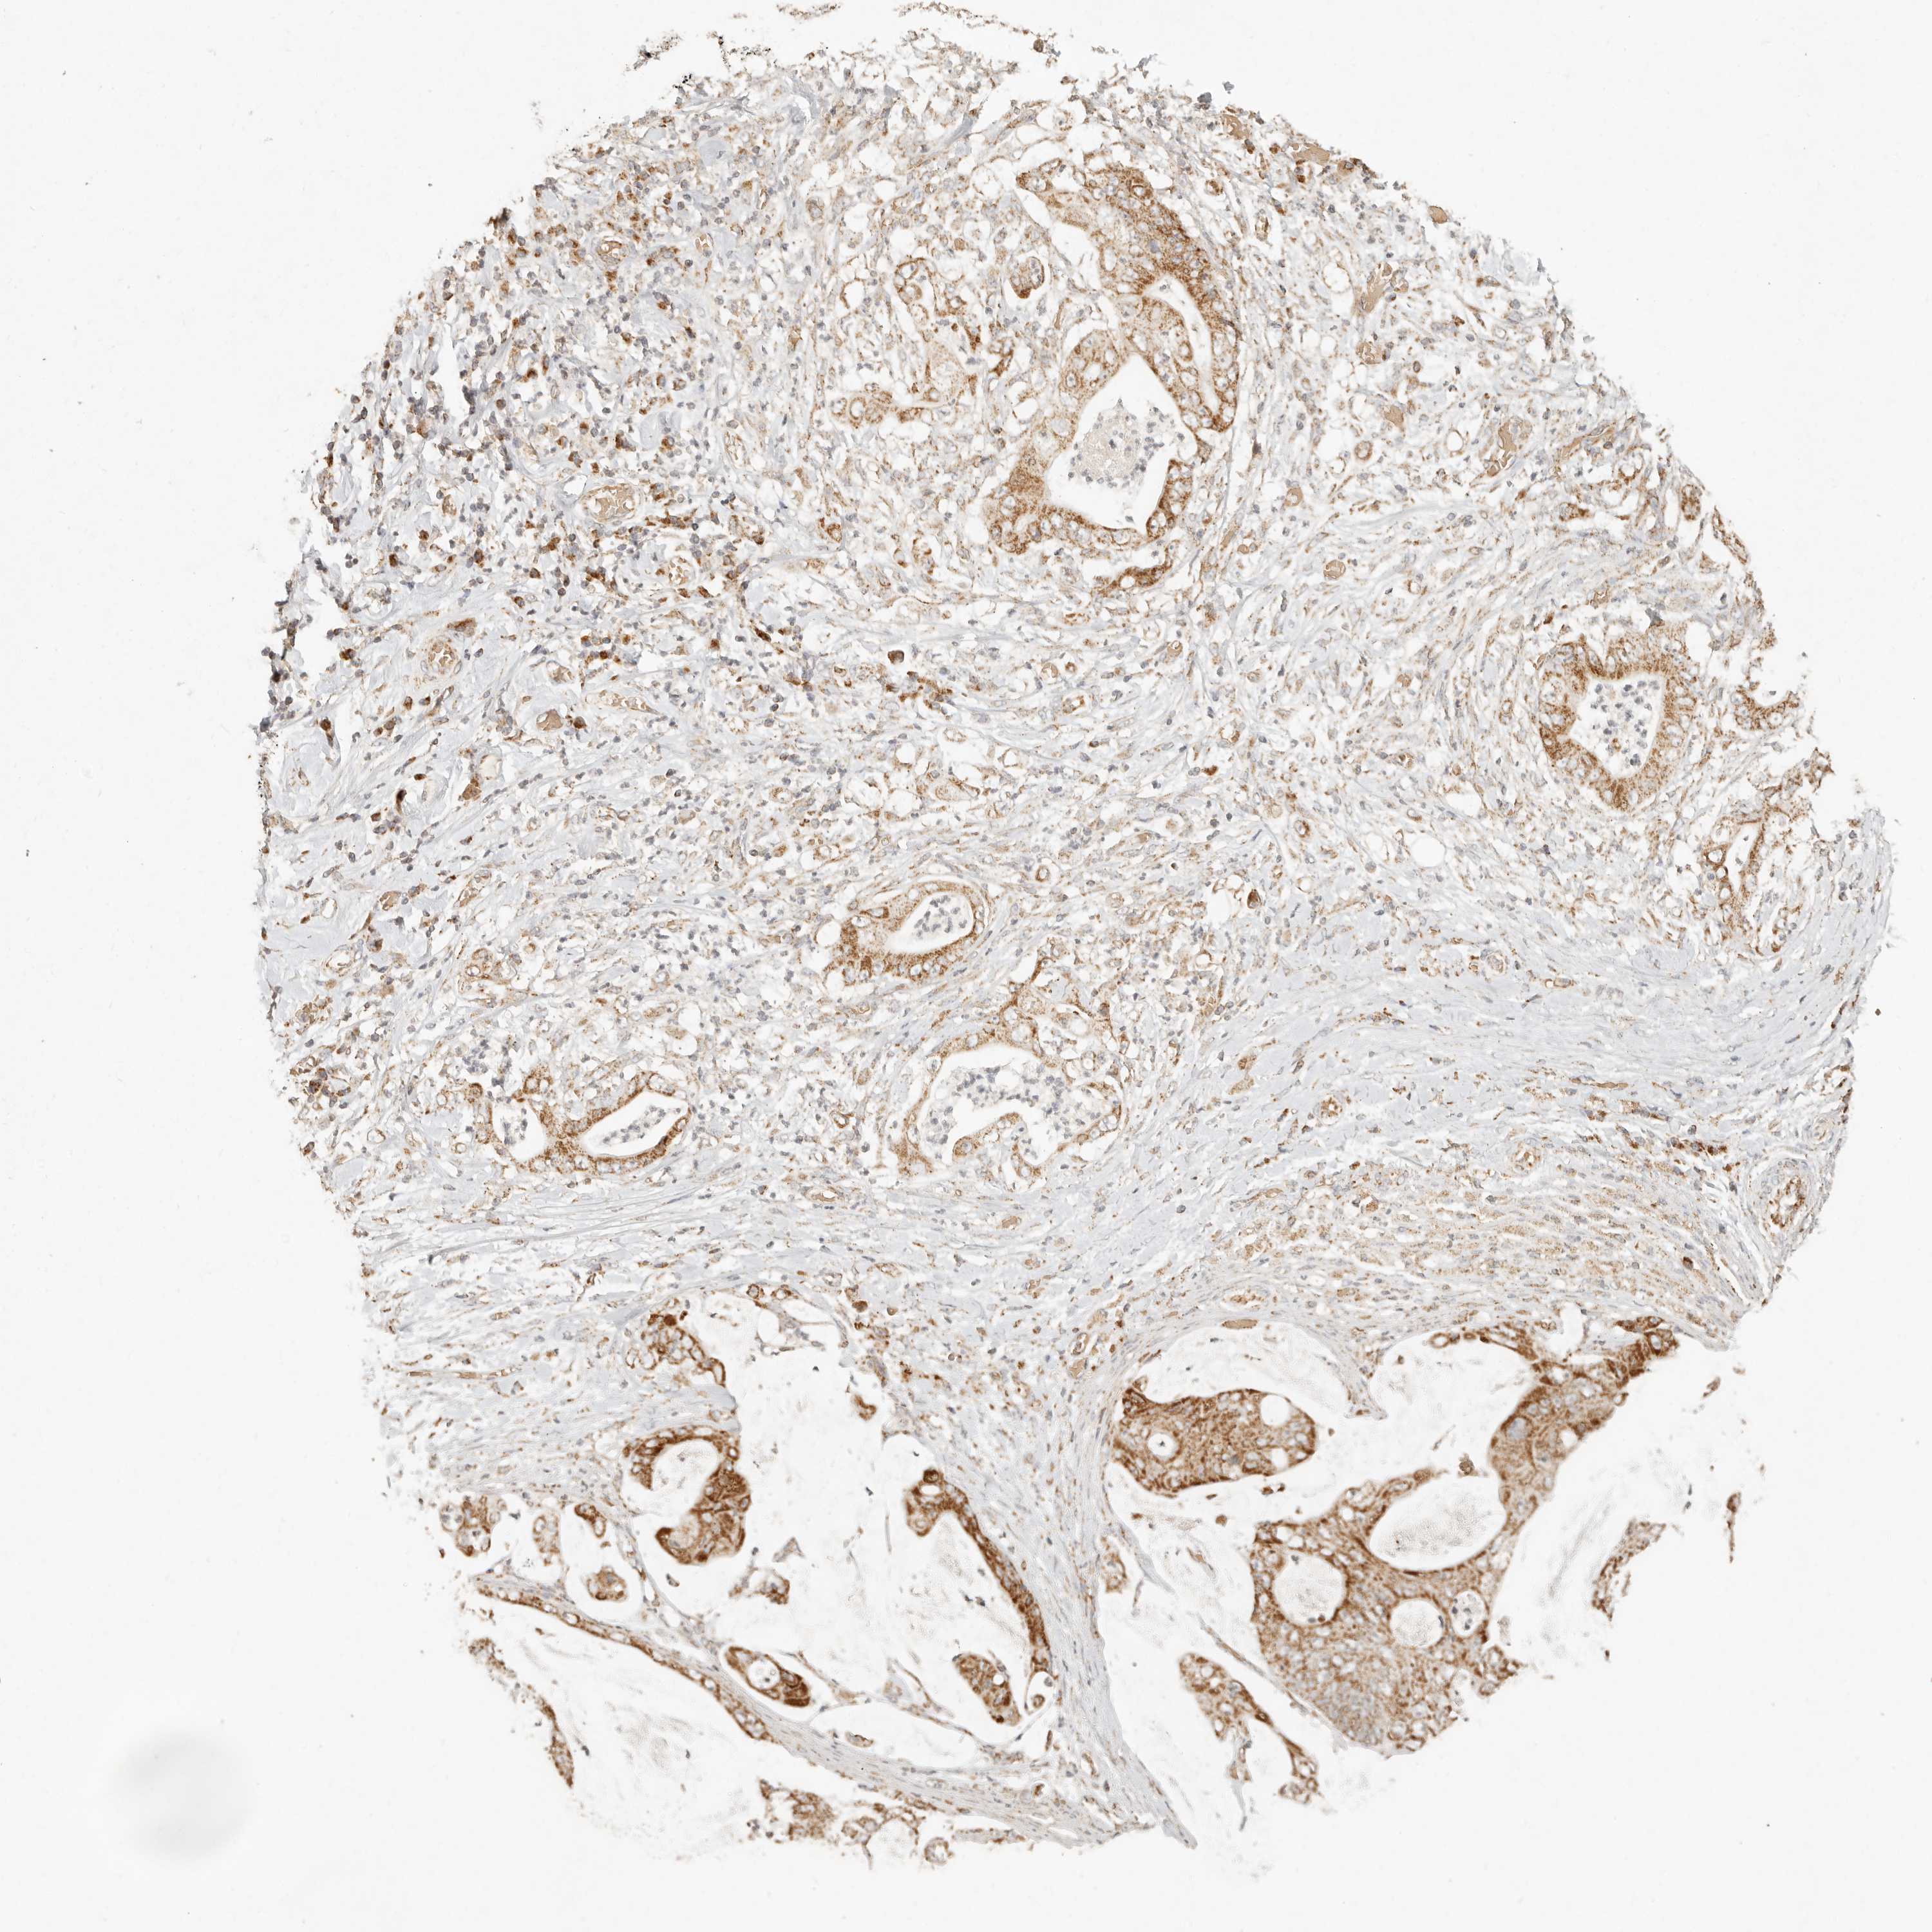

STOMACH CANCER - Protein expressioni

A mouse-over function shows sample information and annotation data. Click on an image to view it in a full screen mode. Samples can be filtered based on level of antibody staining by selecting one or several of the following categories: high, medium, low and not detected. The assay and annotation is described here.

Note that samples used for immunohistochemistry by the Human Protein Atlas do not correspond to samples in the TCGA dataset.

Antibody stainingi

Antibody staining in the annotated cell types in the current human tissue is reported as not detected, low, medium, or high, based on conventional immunohistochemistry profiling in selected tissues. This score is based on the combination of the staining intensity and fraction of stained cells.

Each image is clickable and will lead to virtual microscopy that enables deeper exploration of all samples and also displays staining intensity scores, fraction scores and subcellular localization as well as patient and tissue information for each sample.

Antibody HPA027641

Staining

High

Medium

Low

Not detected

Intensity

Strong

Moderate

Weak

Negative

Quantity

>75%

75%-25%

<25%

None

Location

Nuclear

Cytoplasmic/membranous

Cytoplasmic/membranous,nuclear

Adenocarcinoma, NOS